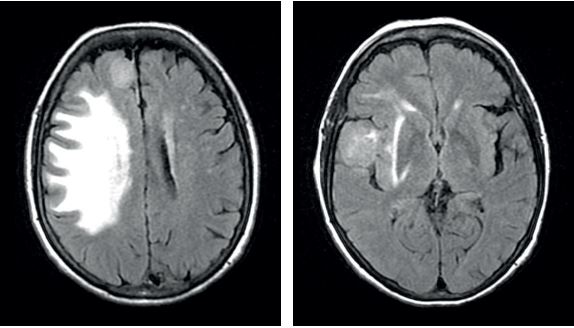

На FLAIR: Два вогнища з підвищеною інтенсивністю сигналу: округлої форми праве лобно-полярне парафальколярне вогнище та праве лобно-очноямкове вогнище. Можна відмітити різницю між ступенем перилезіального набряку, який є значно більшим.

На Т1: Обидва ураження виглядають ізоінтенсивними по відношенню до сірої речовини (СМ) на Т1-зважених зображеннях

Т1 гадоліній: Обидва ураження демонструють інтенсивне та гомогенне контрастне підсилення на Т1-зображеннях. Парафалькоріальне ураження, схоже, пов'язане з мозолистим тілом через дуральний хвіст, що вказує на екстрааксіальне ураження.